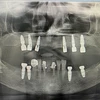

Implant tedavisi